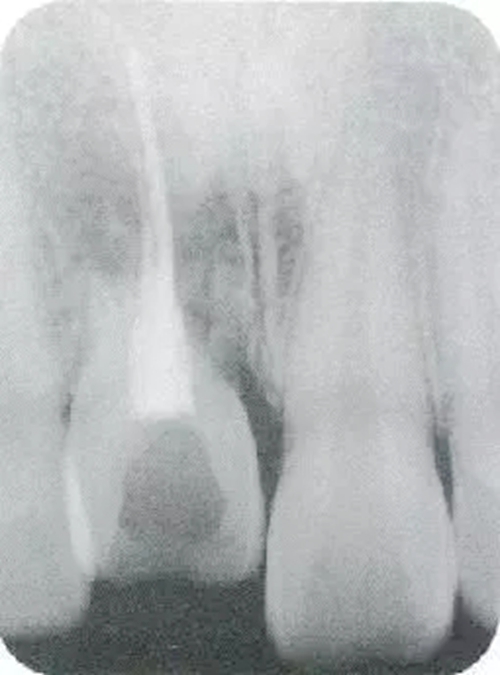

▲圖44-1,2

圖44-3

圖44-1~3 22歲,女性。交通事故3個(gè)月后來院。由于事故導(dǎo)致上頜右側(cè)前牙區(qū)凹陷且存在牙根吸收現(xiàn)象。圖片為初診時(shí)的前方照與根尖片。